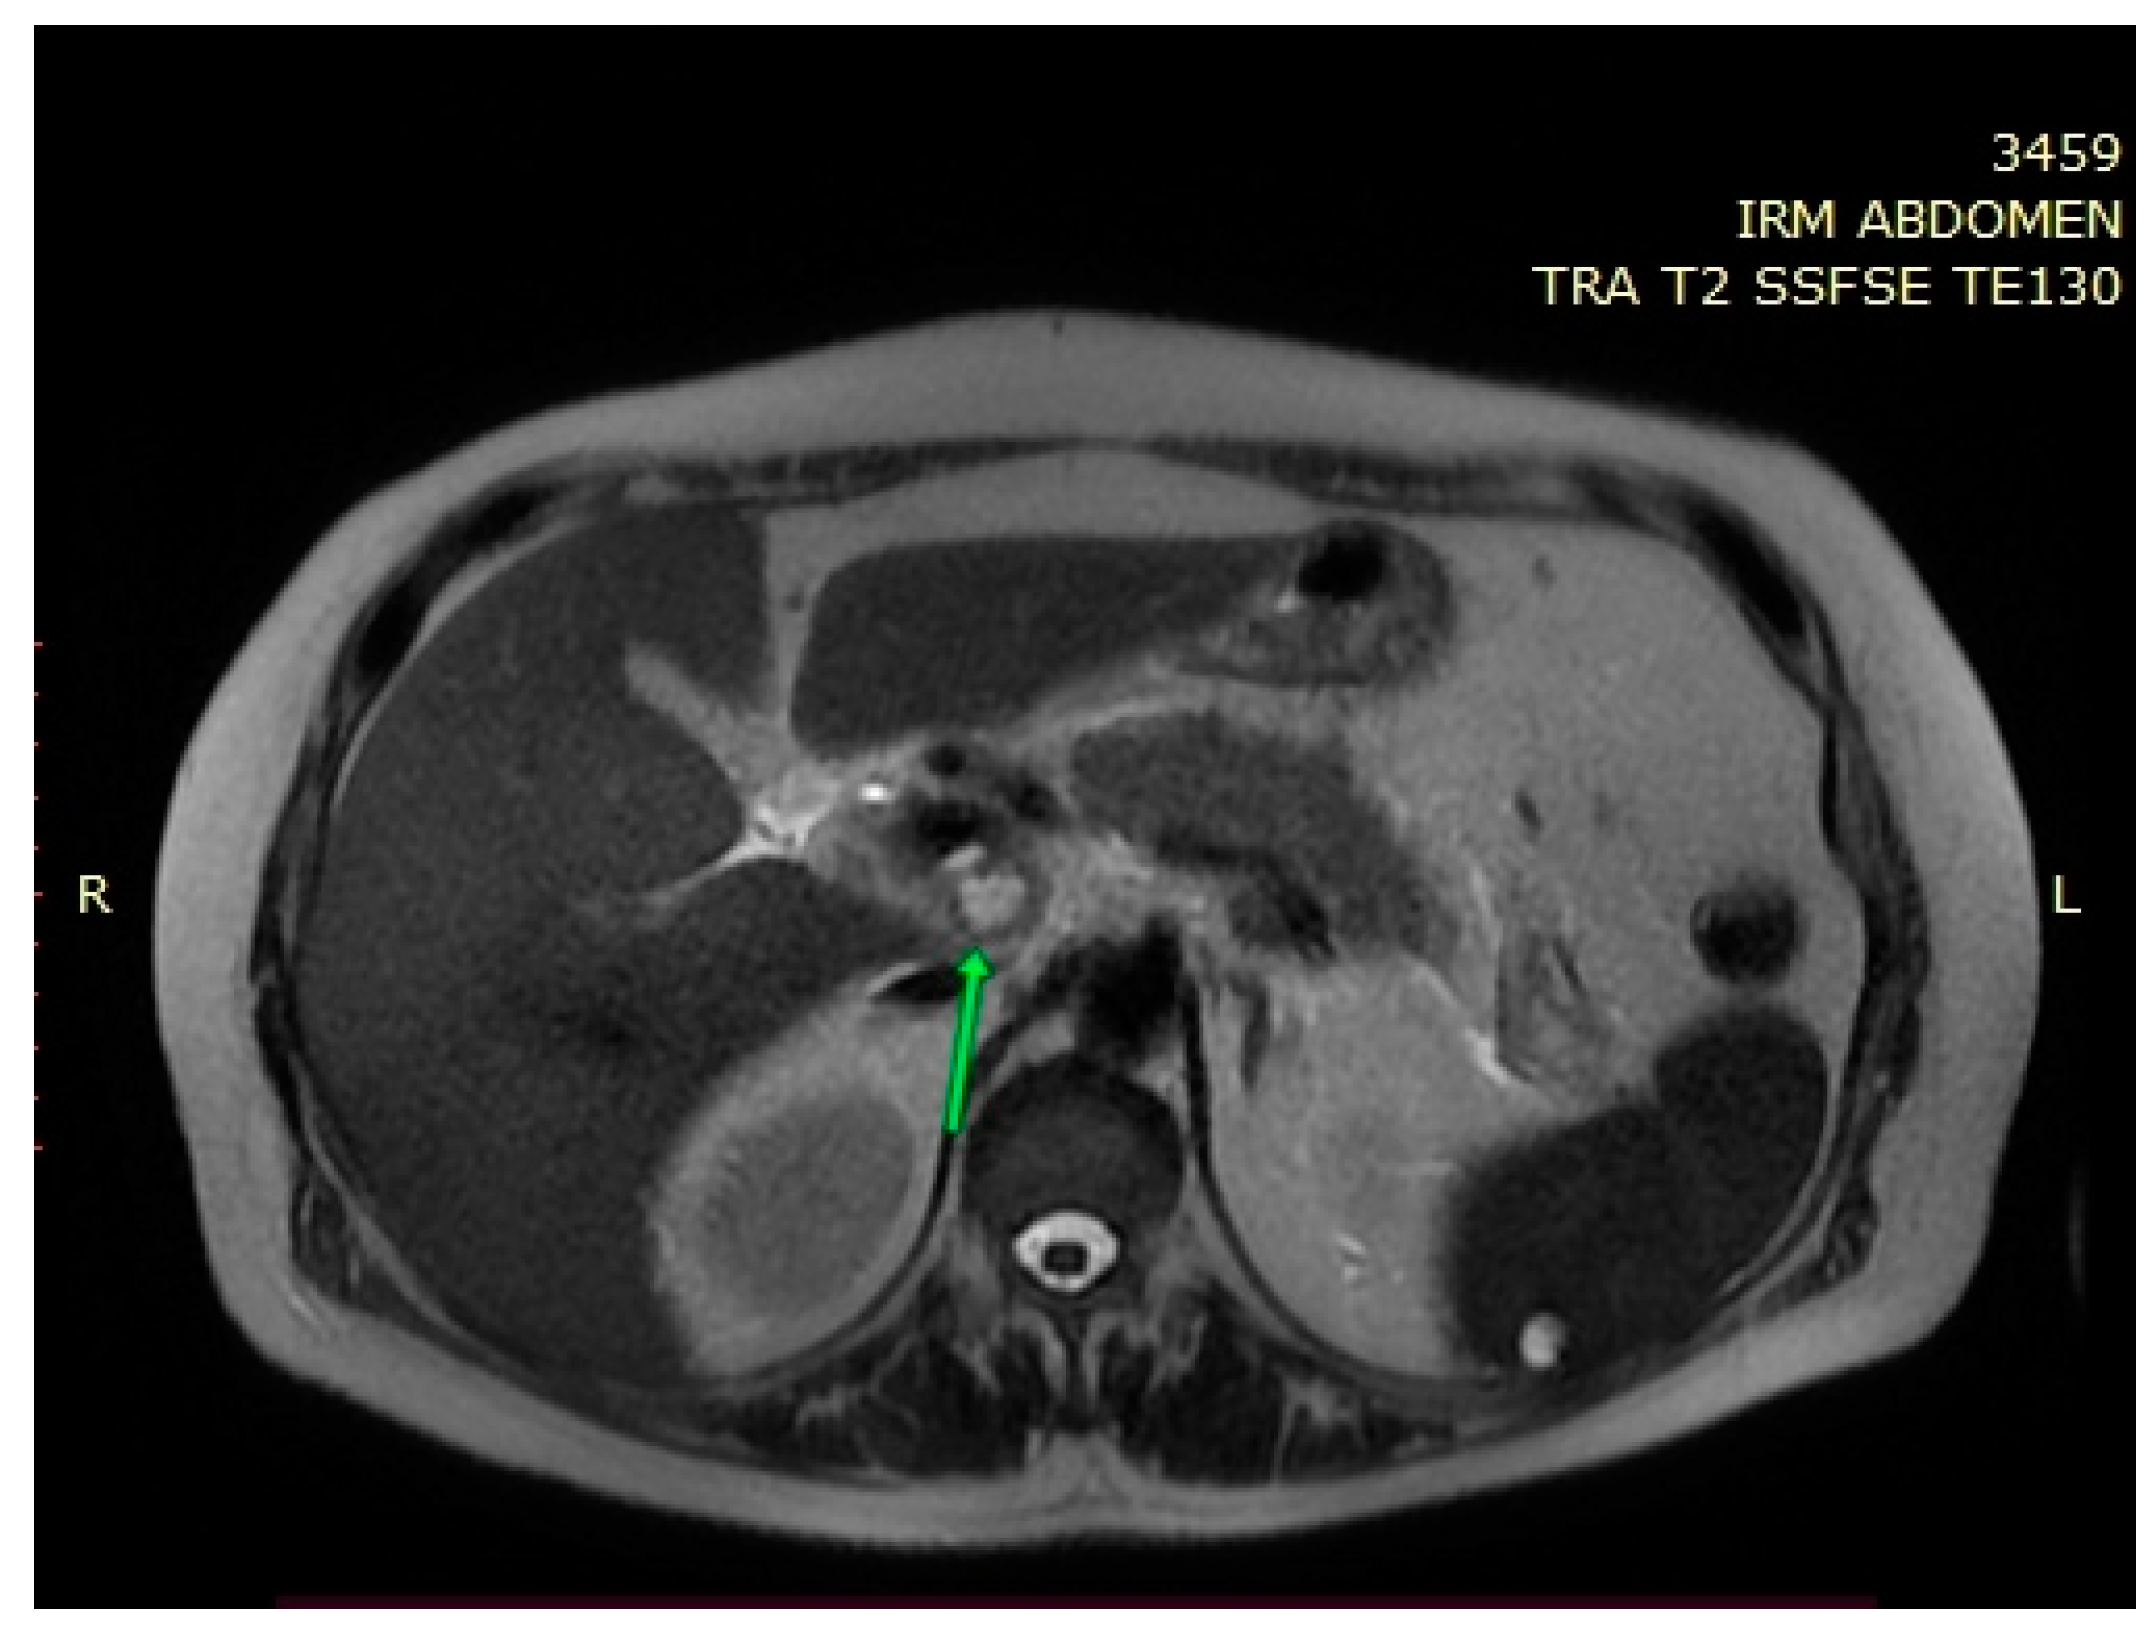

2. Case Presentation